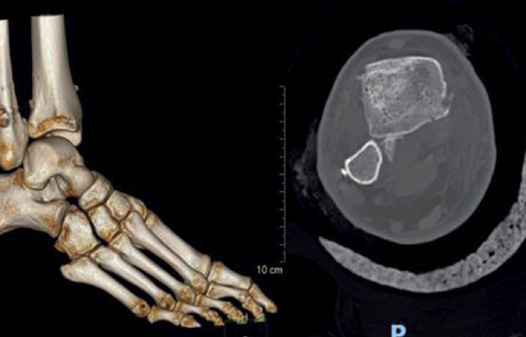

La Tomografía Computada es un estudio de diagnóstico por imágenes que utiliza un equipo especial de Rayos X. Las imágenes son adquiridas por emisión de Rayos X por el tubo del equipo obteniéndose un volumen de datos que se reprocesa al instante y permite obtener imágenes triplanares y volumétricas desde diferentes ángulos, creando imágenes transversales del cuerpo y vistas tridimensionales (3D) de tejidos y órganos.

Nuestra Institución cuenta con tomógrafos multislice o multicorte, la última tecnología en la especialidad. Un mayor número de filas de detectores permite una mejor definición de la imagen obtenida y, en consecuencia, diagnósticos más precisos.

● Tomografía multislice con reconstrucción 3d